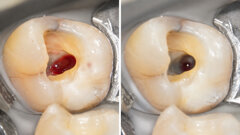

Toute reconstitution dentaire vise à rétablir le rôle et le caractère naturel du système stomatognathique et en ...

DENVER: La découverte récente par le National Institutes of Health que les cellules souches présentes dans les dents ont le potentiel ...

DENVER: La découverte récente par le National Institutes of Health que les cellules souches présentes dans les dents ont le potentiel ...